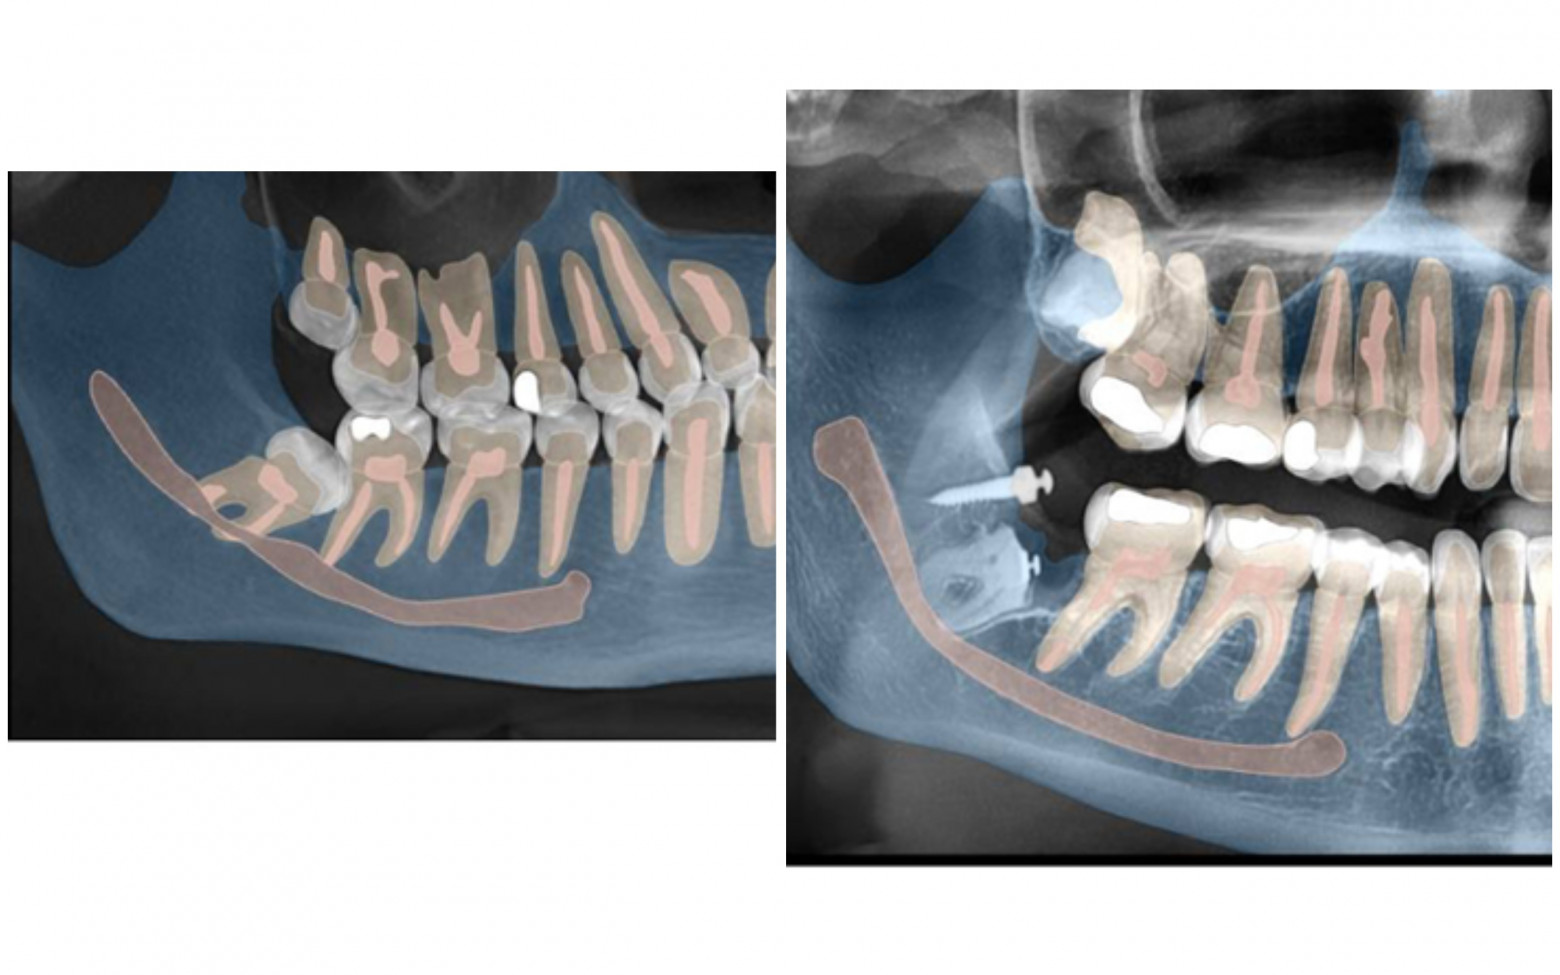

Перед любым лечением мы делаем КТ-снимок челюсти. Дальше в работу включается программа Diagnocat, которая превращает его в детализированную 3D-модель.

Так мы видим нервы, каналы, сложные изгибы челюсти, которые можно не заметить на обычном снимке. На экране можно буквально убрать нижнюю челюсть и посмотреть, как нерв проходит между корнями зуба или где он оказывается особенно близко к потенциально проблемному участку.

Для пациента такая 3D-картинка очень наглядна: вместо того чтобы разглядывать непонятные чёрные полоски на стандартном КТ, он видит полноценную визуализацию.

Если видим такую картину, например, сразу объясняем, что зуб находится в опасной близости к нерву и обычное удаление может быть рискованным.

До и после экструзии:

И ещё одно до и после: